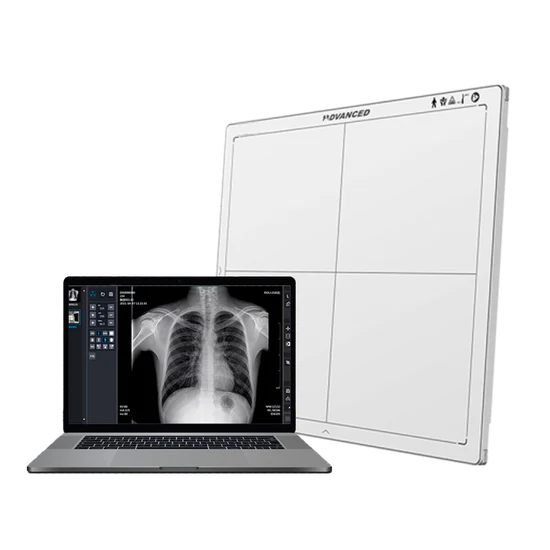

Nuestra tecnología flat panel, operada por técnicos radiólogos certificados y con equipos siempre calibrados, nos permite entregar resultados confiables rápidamente, facilitando la gestión de la salud y la prevención de enfermedades laborales.

Nuestra tecnología

flat

panel

Otorga ventajas frente a la radiografía convencional.

Precisión Superior: Imágenes de alta definición que revelan detalles cruciales para un diagnóstico certero.

Eficiencia Inmediata: Resultados al instante y expedientes electrónicos que eliminan la espera y simplifican la gestión.

Máxima Seguridad: Tecnología de baja dosis que protege el bienestar y la salud de sus colaboradores.